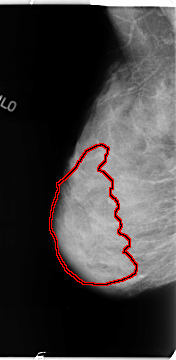

B_3112_1.RIGHT_MLO

RIGHT_MLO LINES 4680 PIXELS_PER_LINE 2280 BITS_PER_PIXEL 12 RESOLUTION 50 OVERLAY

FILE: B_3112_1.RIGHT_MLO.OVERLAY

TOTAL_ABNORMALITIES 1

ABNORMALITY 1

LESION_TYPE CALCIFICATION TYPE PLEOMORPHIC DISTRIBUTION REGIONAL

ASSESSMENT 4

SUBTLETY 3

PATHOLOGY BENIGN

TOTAL_OUTLINES 1

BOUNDARY